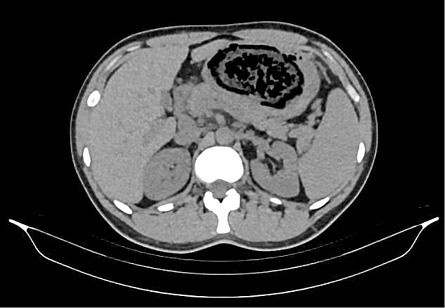

A thirty two years old male patient presented to our surgery department with complain of postprandial abdominal pain, early satiety and occasional vomiting episodes. He lost 5–6 kg in the past 6 months. The symptoms were present for the last 1 year. No comorbidity was reported. Previously he underwent a gastroscopy in another hospital where a stomach bezoar and large ulcer was diagnosed (Figure 1). Plain x-ray (Figure 2), computerized tomography (CT) scan (Figures 3 and 4) and gastroscopy were conducted in our institution. The gastroscopic examination reported giant rough bezoar impossible for endoscopic retrieval.

plain-3.jpg

Figure 3. Axial computerized tomography scan with visual bezoar